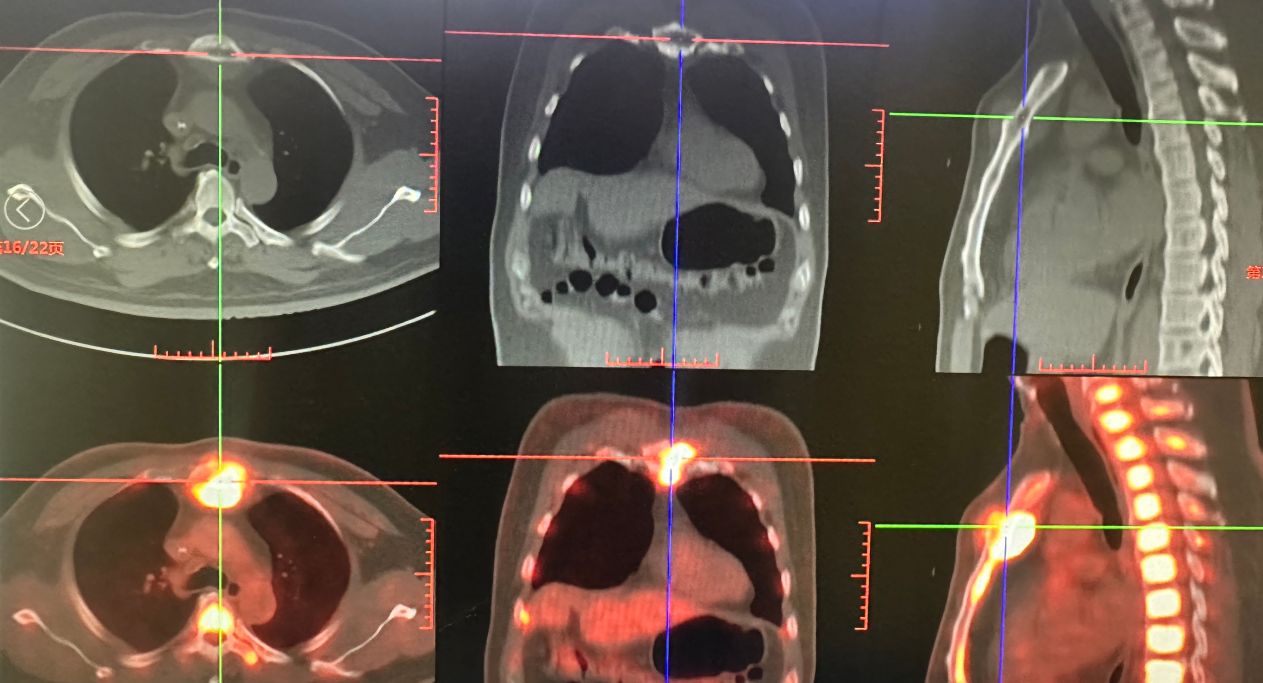

在后续治疗过程中,患者出现胸骨柄处包块(23 mm×12 mm)(图2)。2025年7月31日复查:血常规白细胞7.95×109/L,血红蛋白122 g/L,血小板169×109/L;免疫球蛋白IgA 13.5 g/L,κ轻链5.68 g/L,M蛋白10.6%;乳酸脱氢酶353 U/L;骨髓常规示原幼浆细胞占58.0%,MRD 16.95%。PET/CT示胸骨骨质破坏,周围软组织肿胀,较大横截面积4.3 cm×4.0 cm,SUVmax 20.9;全身多发骨骼弥漫性FDG代谢增高,SUVmax 7.7~12.2(图3)。

图3. PET/CT检查结果